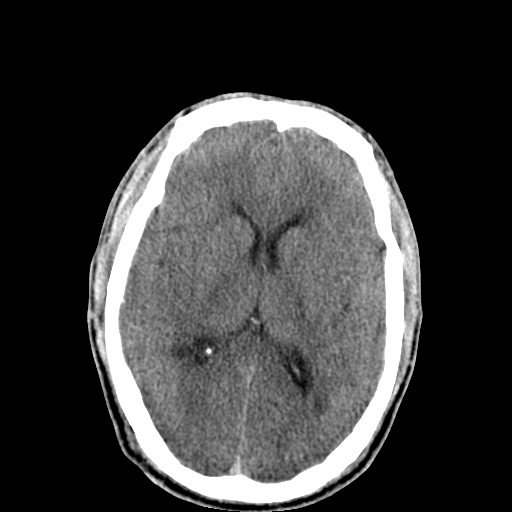

以下是引用李衡钧在2008-9-18 17:37:00的发言:[br]脑质内见两个低密度灶,其内见点状高密度。[br]考虑脑囊虫。建议增强或进一步检查确诊。

以下是引用chmh在2008-9-18 18:45:00的发言:[br]考虑脑囊虫病可能性大,建议行ct增强检查及血清和脑脊液囊虫补体结合试验.